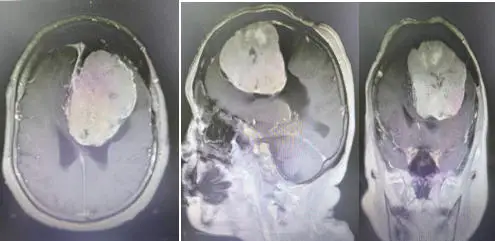

头颅CT检查提示额叶巨大占位,颅内肿瘤已达8cm,体积巨大,且患者年事已高,手术稍有不慎就可能出现大出血、生命体征波动、神经功能损伤等致命风险。神经外科苏永永主任团队积极联合多学科讨论,模拟术中突发风险,制定严密的手术方案。

手术台上,在麻醉手术部、输血科等部门密切配合下,苏永永团队为患者实施了“额叶病损切除术”,面对肿瘤周围复杂的血管神经结构,凭借精湛的显微操作技术,精细剥离,当肿瘤被完整切除的那一刻,所有人悬着的心终于放下。术后,护理团队无缝衔接,从生命体征监测、并发症预防到康复指导,全程精细化照护,如今陈阿姨语言清晰、肢体活动自如,已顺利度过危险期,即将康复出院。